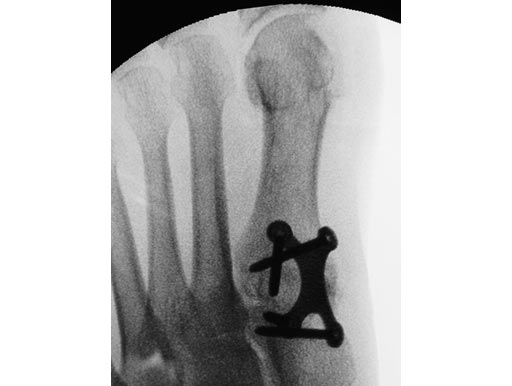

First MTP fusion and modified McBride with a distal softtissue release and second metatarsophalangeal (MTP) capsulotomy. A mini tight rope was used to hold and reduce the alignment of the first metatarsal. The X-plate was used to hold rigid fixation of the fusion. A K-wire was used for the second MTP capsulotomy.